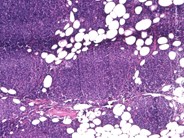

Category: Lymphoma: Mature B-cell and Plasma cell Neoplasms > Low-grade B-cell lymphoma > Follicular Lymphoma

dendritic meshwork underlying neoplastic follicles.